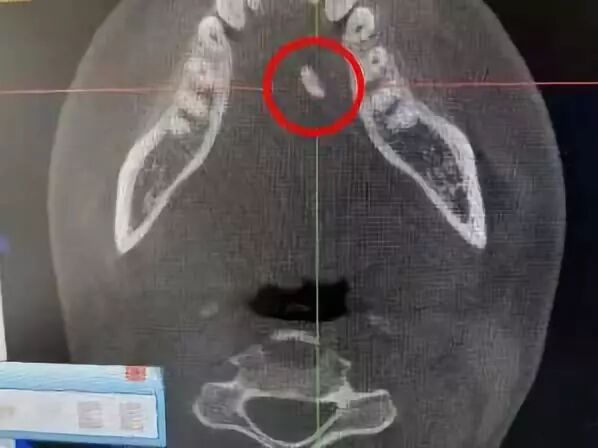

初步诊断为右侧颌下腺导管结石并颌下腺炎随后的CT检查中发现患者右侧颌下腺增大舌下软组织内多密度影结石/钙化建议进行手术治疗

(红圈内为结石)